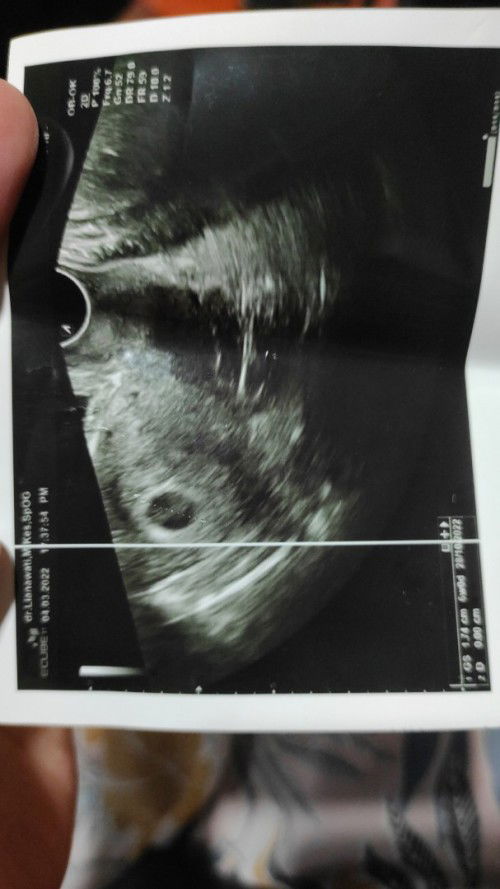

kmrn usg transvaginaL 6week baru keLiatan kantong kehamilan.normalkah bund?

sangat normal. 8-9w udh ada janin